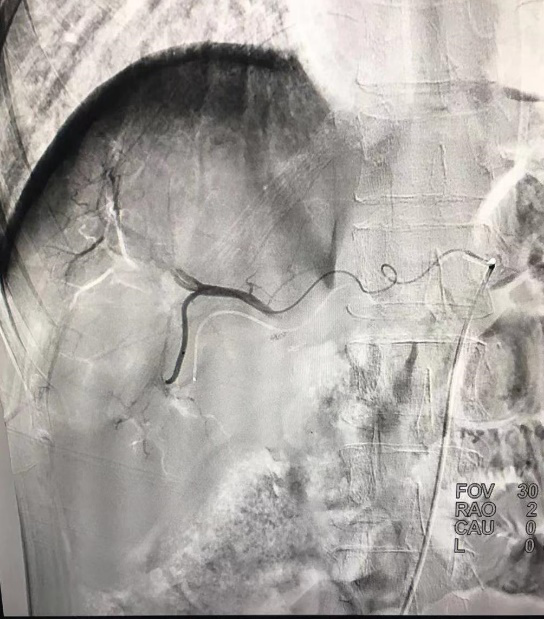

術(shù)后造影顯示血管栓塞良好,腫瘤未見明顯染色。